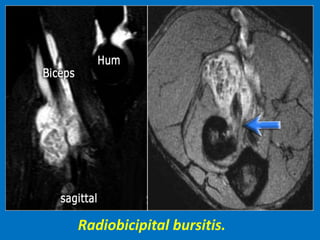

Radiobicipital bursitis.